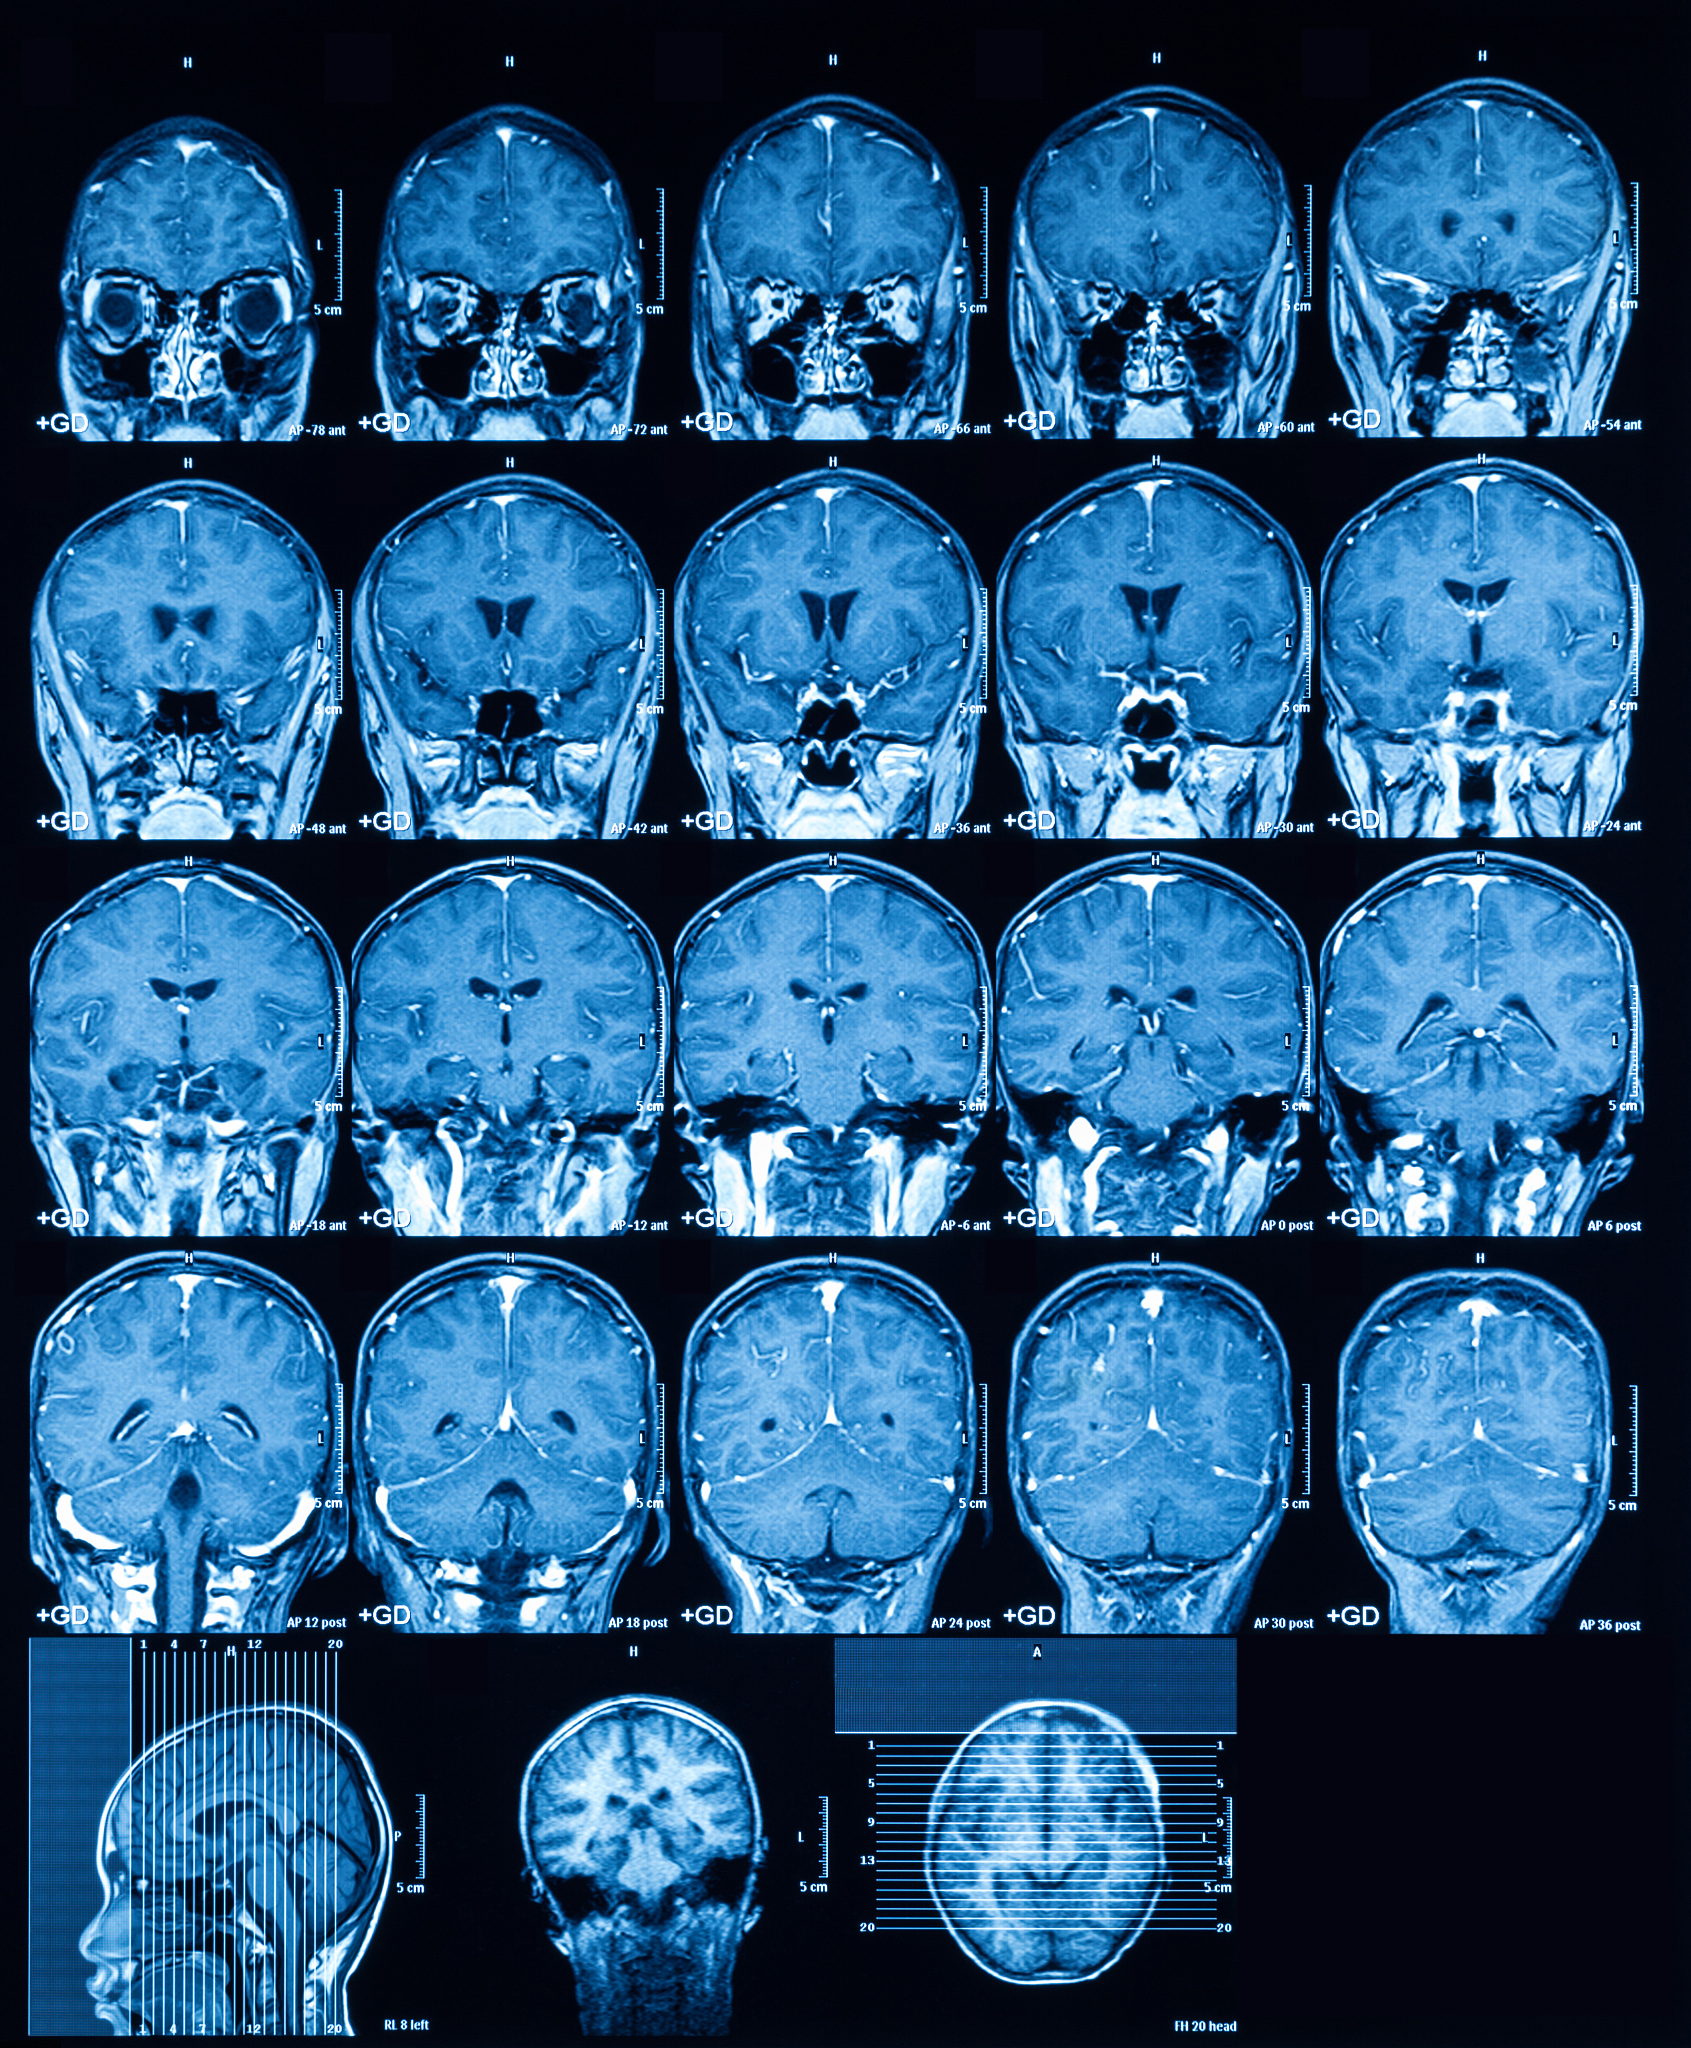

一直以来,分子影像学技术因其可视化的优势,在生物医学研究和临床实践中发挥了重要作用。其中经典非侵入性成像方式,如正电子发射断层扫描(PET)、单光子发射计算机断层扫描(SPECT)和磁共振成像(MRI)等成像方式,普遍存在潜在的活体辐射危害、成本高和难以实时成像等问题。

随着科技的不断进步,新型分子影像学技术的发展,如光学成像、超声成像、微波成像、电阻抗成像、磁共振弹性成像、磁共振电导率成像、磁共振温度成像等,正在逐渐成为新的研究热点。

电阻抗成像技术则是通过测量组织内部电阻抗的变化来实现成像,主要应用于肺部和乳腺成像。磁共振弹性成像、磁共振电导率成像和磁共振温度成像则是利用磁共振技术来实现对组织的成像,可以提供更多的生物组织信息。